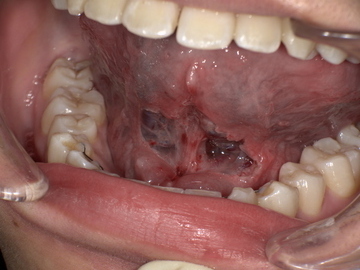

施術: 短くなった舌小帯をメスで切除・形成します。通常、約15分で完了する安全性の高い小手術です。

舌小帯形成術は安全な治療ですが、術後に出血や腫れ、まれに再癒着が起こる可能性があります。これらのリスクについては、カウンセリング時に丁寧にご説明します。